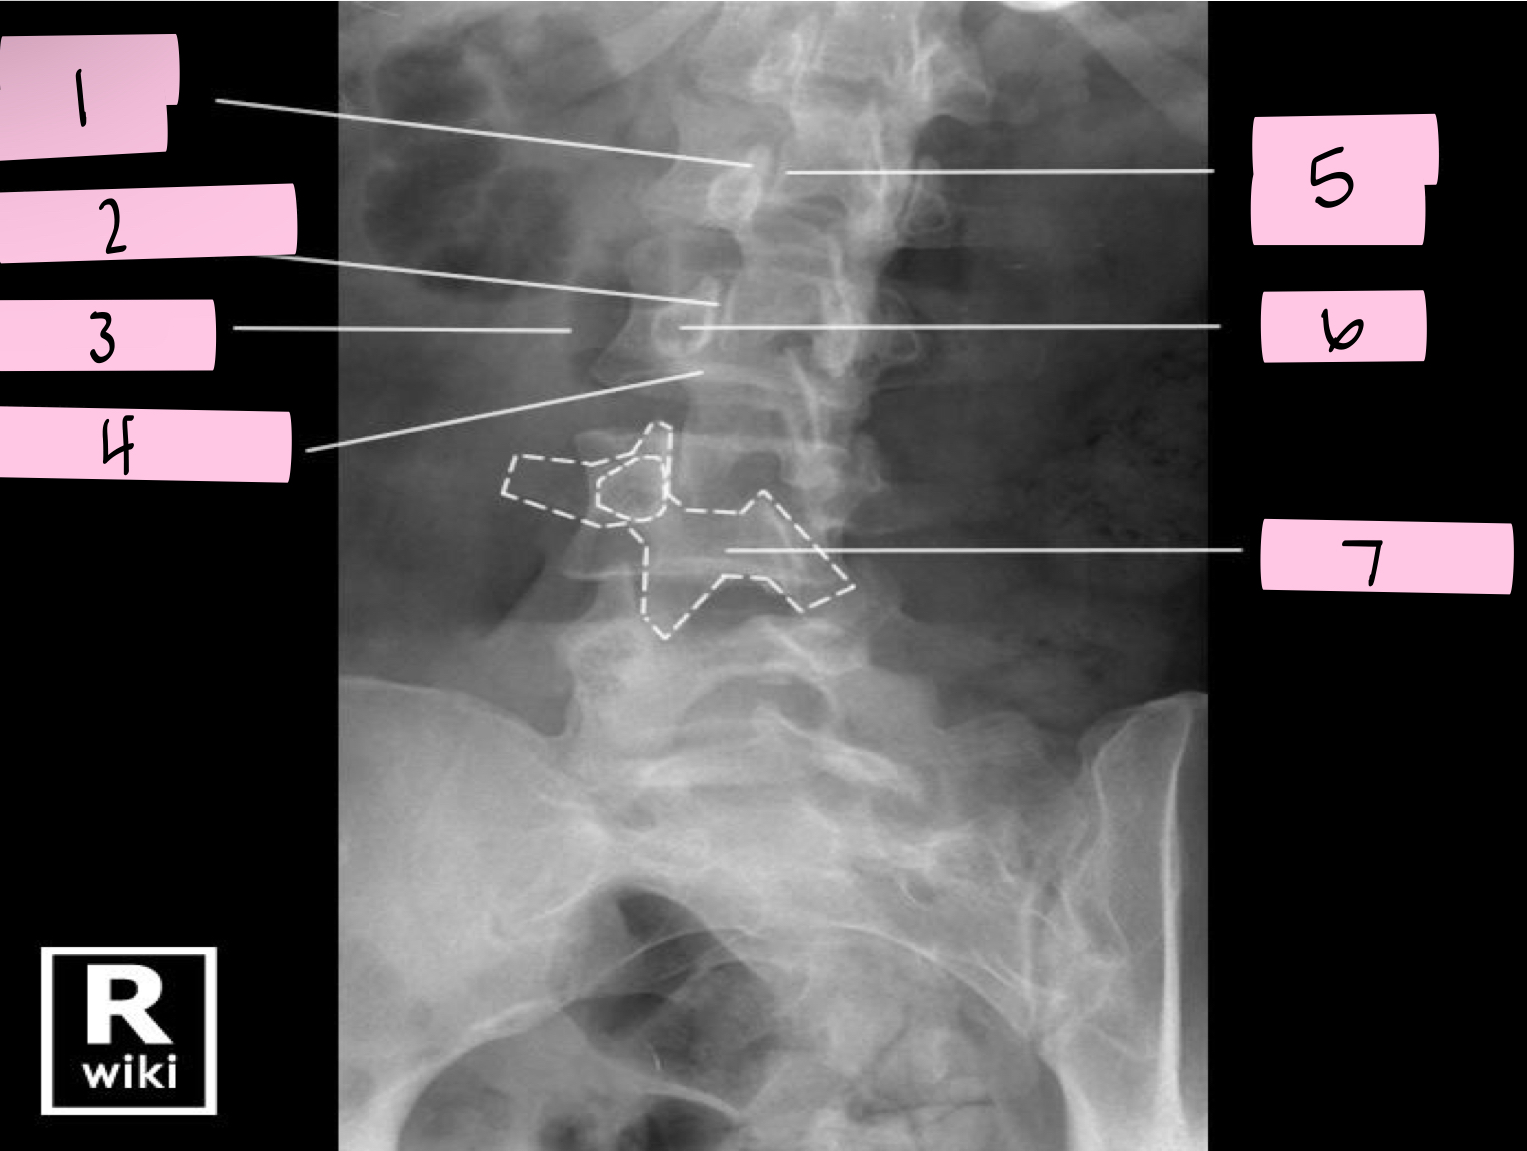

What is 1 pointing to?

Nose- Transverse process

What is 2 pointing to?

Eye- Pedicle

What is 3 pointing to?

Neck- Pars interacticularis (isthmus)

What is 4 pointing to?

Foreleg- Inferior articular process

What is 5 pointing to?

Ear- Superior articular process

What is 6 pointing to?

Tail- Superior articular process of opposite side

What is 7 pointing to?

Body- Lamina and spinous process

What is 8 pointing to?

Hindleg- Inferior articular process of opposite side